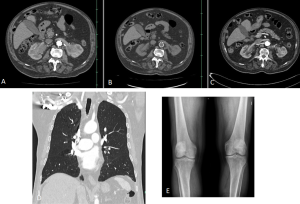

ERDHEIM-CHESTER DISEASE (ECD)

ECD is a rare non-Langerhans cell histiocytosis affecting multiple organ systems, typically presenting in adults in their 5th–7th decades with slight male predominance.

Diagnosis relies on biopsy supported by characteristic clinical and imaging features.

Retroperitoneal and renal involvement occurs in a significant proportion, with CT and MRI demonstrating bilateral perinephric and posterior pararenal soft-tissue infiltration, producing the classic “hairy kidney” appearance. Infiltrates are generally isoattenuating or iso- to hypointense to skeletal muscle with mild contrast enhancement; FDG uptake may be present but can be obscured by physiological renal activity. Chronic infiltration may result in renal atrophy.

Although both ECD and retroperitoneal fibrosis can lead to hydronephrosis, their distribution differs: ECD typically affects the perinephric fat and renal hila, whereas idiopathic RPF encases the anterolateral aorta and proximal ureters. Aortic encasement (“floating aorta sign”) and periureteric involvement may occur, but ECD usually spares the IVC and pelvic ureters. Additional distinguishing features include irregular perirenal infiltration and bilateral symmetric adrenal thickening.

Skeletal involvement, particularly of the femur, tibia and fibula, is seen in most patients, often causing bone pain [9].